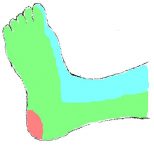

The foot consists of 6 angiosomes in total (Figure 1):

- The posterior tibial supplies 3 angiosomes through the medial calcaneal, medial plantar, and lateral plantar braches (medial ankle and plantar surface).

- The anterior tibial artery supplies the dosalis pedis angiosome encompassing the entire dorsal aspect of the foot.

- The peroneal artery supplies 2 angiosomes through the lateral calcaneal and anterior perforating branches (lateral heel and anterolateral ankle).

Sometimes, the severity and distribution of the infra-popliteal disease prevent an angiosome-guided revascularization strategy. For example, in a patient with a medial heel ulcer, angiography may reveal proximal occlusions of the peroneal and posterior tibial arteries, and a severely diseased anterior tibial artery that is supplying the only perfusion to the foot (Figure 1). Revascularizing the anterior tibial artry is technically most feasible, though this in essence ignores the angiosome principle which would require recanalizing a lengthy chronic occlusion of the posterior tibial artery. Thus, angiosome-guided revascularization is not uniformly achievable in all patients, particularly in those receiving endovascular techniques.